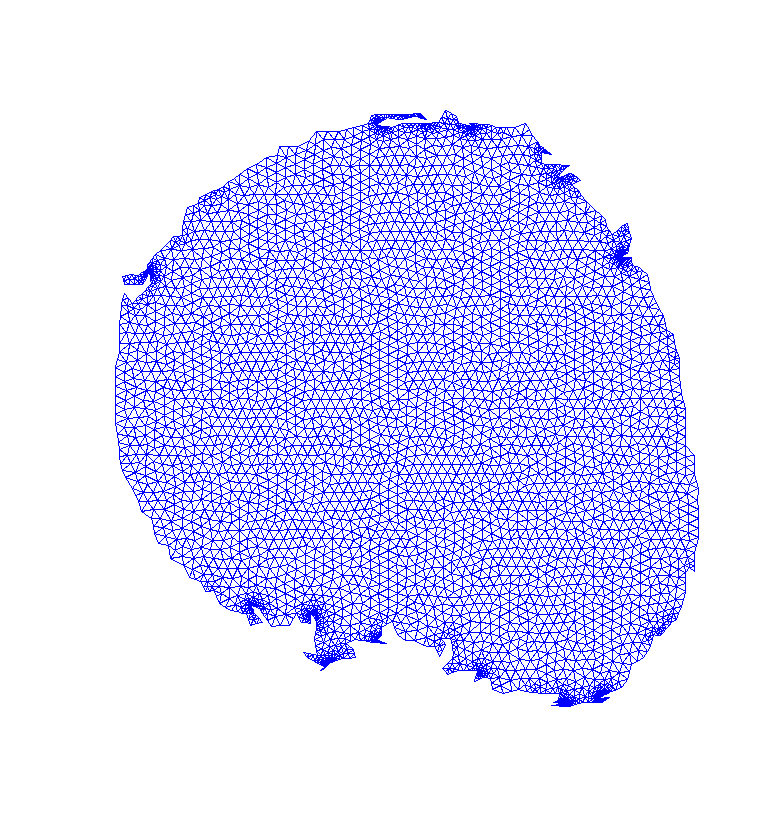

To reduce computational cost and get even more accurate results, we may create a Finite Element (FE) grid on the area of interest rather than on the image boundaries. For illustration, we consider the MR-images and shown on the top/left and bottom/left of Fig. 4, respectively. We automatically produce a mesh on the breast boundaries (see on the left of Fig. 5). The segmentation for and for is shown on the center and right of Fig. 5, respectively.

This FE approach can be easily adapted to other images, for example in Fig. 6 left, we apply this approach for segmenting a ventricle MRI heart image, taken from Angenent2006 with permission from1. In the center of Fig. 6, the FE mesh is shown and on the right of the figure, we see the segmentation of the adaptive eigenspace using FE. As discussed in Rem. 1, we do not always get a binary segmentation, but this is easy to get using a standard threshold.